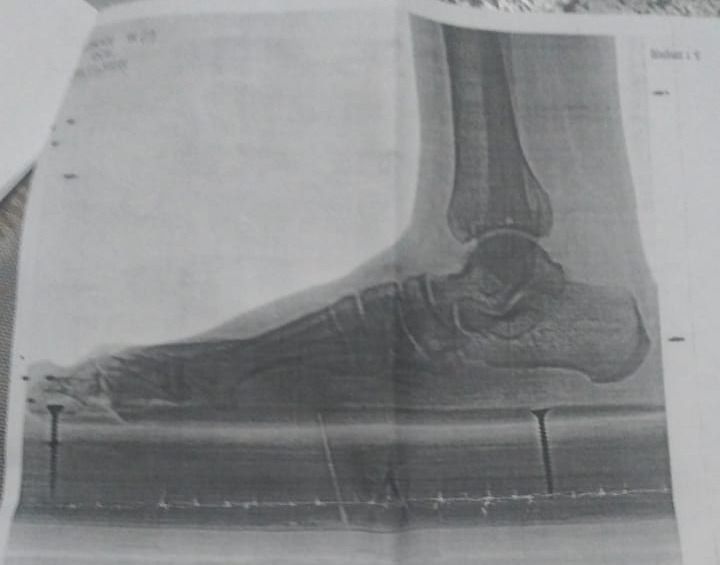

“Oğlum Elman İmaməliyevin ikitərəfli yastıpəncəlik səbəbilə hərbi xidmətə yarasızdır. Bu, Tərtər Rayon Mərkəzi Xəstəxanasından verilən rentgen kağızı ilə təsdiq olunub. Lakin hərbi xidmətə çağırış idarəsinin mayoru oğlumun hərbiyə xidmət üçün yararlı olduğunu əks etdirən saxta sənəd əldə edib. Hansı ki, oğlumun sol ayağı 3-cü, sağ ayağı isə 2-ci dərəcəli ikitərəfli yastıpəncədir.

Hərbi xidmətə çağırış idarəsinin komissiya həkimi rentgen kağızlarını da verib. Amma idarədəki mayor Şahverdiyev uşaqla prinsipə düşdüyü üçün saxta sənəd alıb. O, uşağı təhqir edib, uşaq da deyib ki, səni vuraram. İndi tələb edirəm ki, siz hansı sənədə əsasən müəyyən etmisiz ki, oğlumda hər iki ayağı üçüncü dərəcə yastıpəncədir? Həmin sənədi mənə vermirlər. Deyirlər ki, uşaq yararlıdır, aparırıq. Amma ona verilən möhlət kağızında isə 45-ci və 49-cu maddəyə əsasən, uşağın müalicə almalı olduğu yazılıb”.